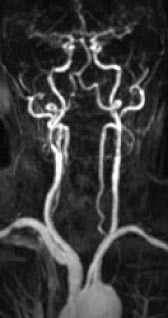

En av de vanligste indikasjonene for kateterangiografi er arteriosklerotisk sykdom i underekstremitetsarteriene. Stenoser vil kunne behandles i samme seanse med perkutan transluminal angioplastikk (PTA). MRA gir ikke mulighet for behandling, men metoden har et stort diagnostisk potensial. Hittil har man mest benyttet 2D-innstrømnings-MRA for fremstilling av arteriene i underekstremitetene. Metoden er tidkrevende (ca. 40 minutter for å dekke området fra distale aorta til ankler med tynne tverrsnitt) og gir ofte overestimering av stenosegrad og lengden av okklusjoner. Metoden er et særlig godt supplement når kateterangiografi er umulig eller inadekvat pga. utbredte karokklusjoner. 2D-innstrømnings-MRA er svært sensitiv for langsom blodstrøm, og vil f.eks. kunne påvise åpne perifere arterier ved uttalte proksimale okklusjoner. Den beste MRA-metoden er likevel kontrastforsterket MRA, forutsatt ny og rask MR-apparatur med mulighet for å flytte pasientbordet under bildeopptaket. Denne metoden gjør det mulig å undersøke bekken- og underekstremiteter i løpet av én kontrastbolusinjeksjon, og kvaliteten på disse opptakene er nesten identisk med den som oppnås med kateterangiografi (20). Utviklingen går mot at man velger MRA til den diagnostiske angiografiske utredningen, mens kateterangiografi reserveres de tilfellene der intervensjonsbehandling er aktuelt.

Arteriosklerotisk sykdom i halsarteriene er en av de vanligste indikasjonene for MRA. Ultralydundersøkelse (med fargedoppler og spektraldoppler) er et godt ikke-invasivt alternativ, og for stenoser i carotisbifurkaturen synes denne metoden å være nokså likeverdig med MRA (14). Ultralydundersøkelsens svakhet i forhold til MRA er begrenset anatomisk dekning, verken den intrakraniale del av halsarteriene eller avgangen fra aortabuen kan fremstilles adekvat. Fremstillingen av vertebralisarteriene blir også ufullstendig. Inntil nylig har innstrømnings-MRA vært den foretrukne MRA-metoden for fremstilling av carotis- og vertebralisarteriene, men den er i ferd med å bli erstattet av kontrastforsterket MRA. Sistnevnte metode er mindre ømfintlig enn innstrømnings-MRA for ulike artefakter, som bl.a. kan føre til overestimering av stenosegrad, og den kontrastforsterkede varianten gir også en mye bedre fremstilling av arterieavgangene fra aorta (fig 5). MR med innstrømnings-MRA kan erstatte kateterangiografi ved mistanke om carotisdisseksjon (15), det er foreløpig liten erfaring med kontrastforsterket MRA ved denne indikasjonen. Kontrastforsterket MRA gir en god fremstilling av a. subclavia og er et godt alternativ ved spørsmål om stenose i skalenusporten. To kontrastinjeksjoner med redusert dose gjør det mulig å undersøke arterien med både løftet og senket arm i samme seanse. Halsvenene kan fremstilles med 2D-innstrømnings-MRA eller med kontrastforsterket MRA, men der det er spørsmål om trombosering eller venens relasjon til en tumor, vil ofte ultralydundersøkelse være tilstrekkelig. MRA gir imidlertid en bedre anatomisk oversikt og er også mer reproduserbar. 2D-innstrømnings-MRA er også